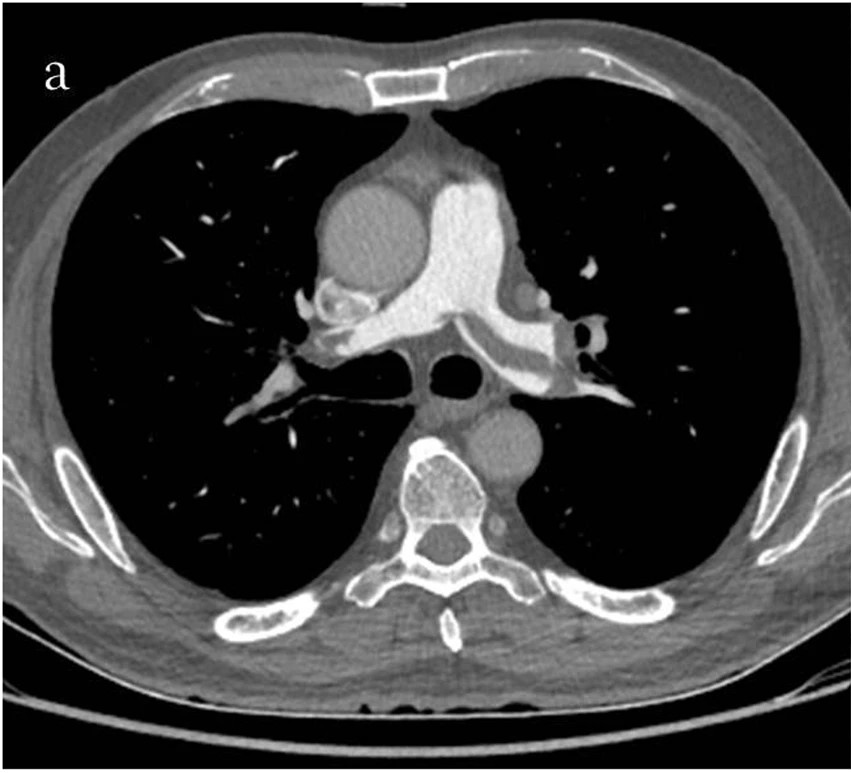

Dx?

Pulmonary Embolism